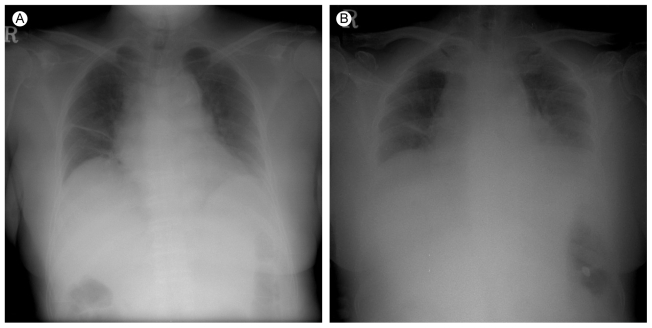

The initial chest X-ray showed a slightly reduced lung volume (Fig. 1A). The chest computed tomography (CT) scan showed no evidence of pulmonary thromboembolism, but there was bibasilar atelectasis (Fig. 2). Echocardiography revealed normal systolic and diastolic heart function.

Figure 1

Plain chest radiography. (A) On the first day of the hospital admission, the chest X-ray revealed normal findings except for a focal atelectasis in the right middle lung field. (B) On the sixth day, the chest X-ray showed reduced lung volume.

During the next five days, her dyspnea became more severe. On the sixth day of hospitalization, the patient had severe respiratory distress with labored breathing. The respiratory rate was 40 breaths/min and the mental status was confused. The arterial blood gas analysis on an O2 mask with 10 L was pH 7.324, PaCO2 54.9 mmHg, PaO2 94.4 mmHg, and oxygen saturation 96.6%. The chest X-ray revealed no definite infiltration but the lung volume was reduced (Fig. 1B). The patient was transferred to the intensive care unit and mechanically ventilated.